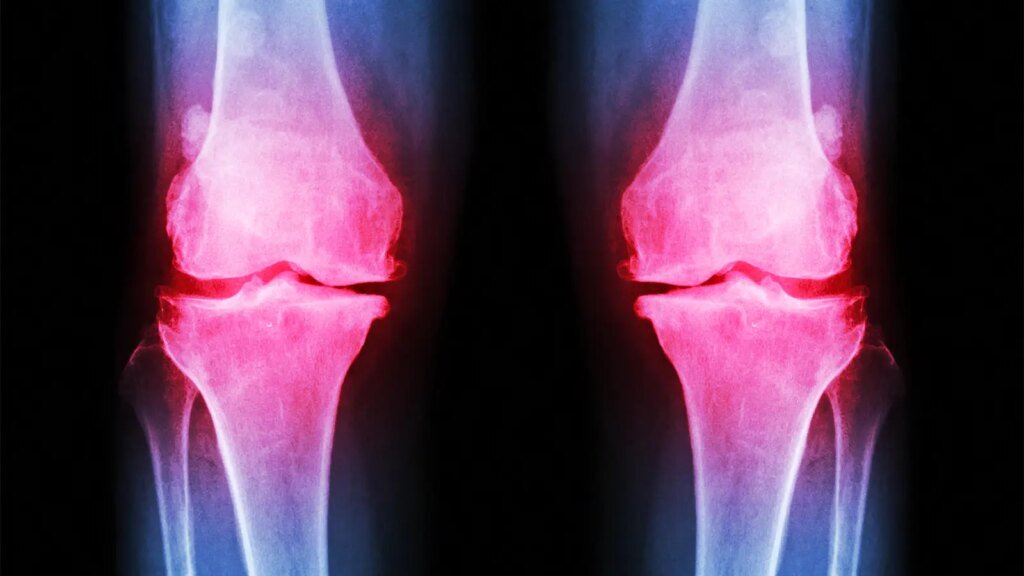

An investigational infusion drug provided more pain relief for patients with osteoarthritis (OA) of the knee than did placebo in a 17-week, phase II clinical trial, researchers said.

Mean patient age was about 64 and a little over half the sample were women. WOMAC pain scores in the target knee at baseline averaged 5.74-5.82 in the four study arms; scores in the contralateral knee were about 2 points lower. Half the sample had joint degeneration at baseline rated as Kellgren-Lawrence grade 3 in the target knee, and about 30% were at grade 4.